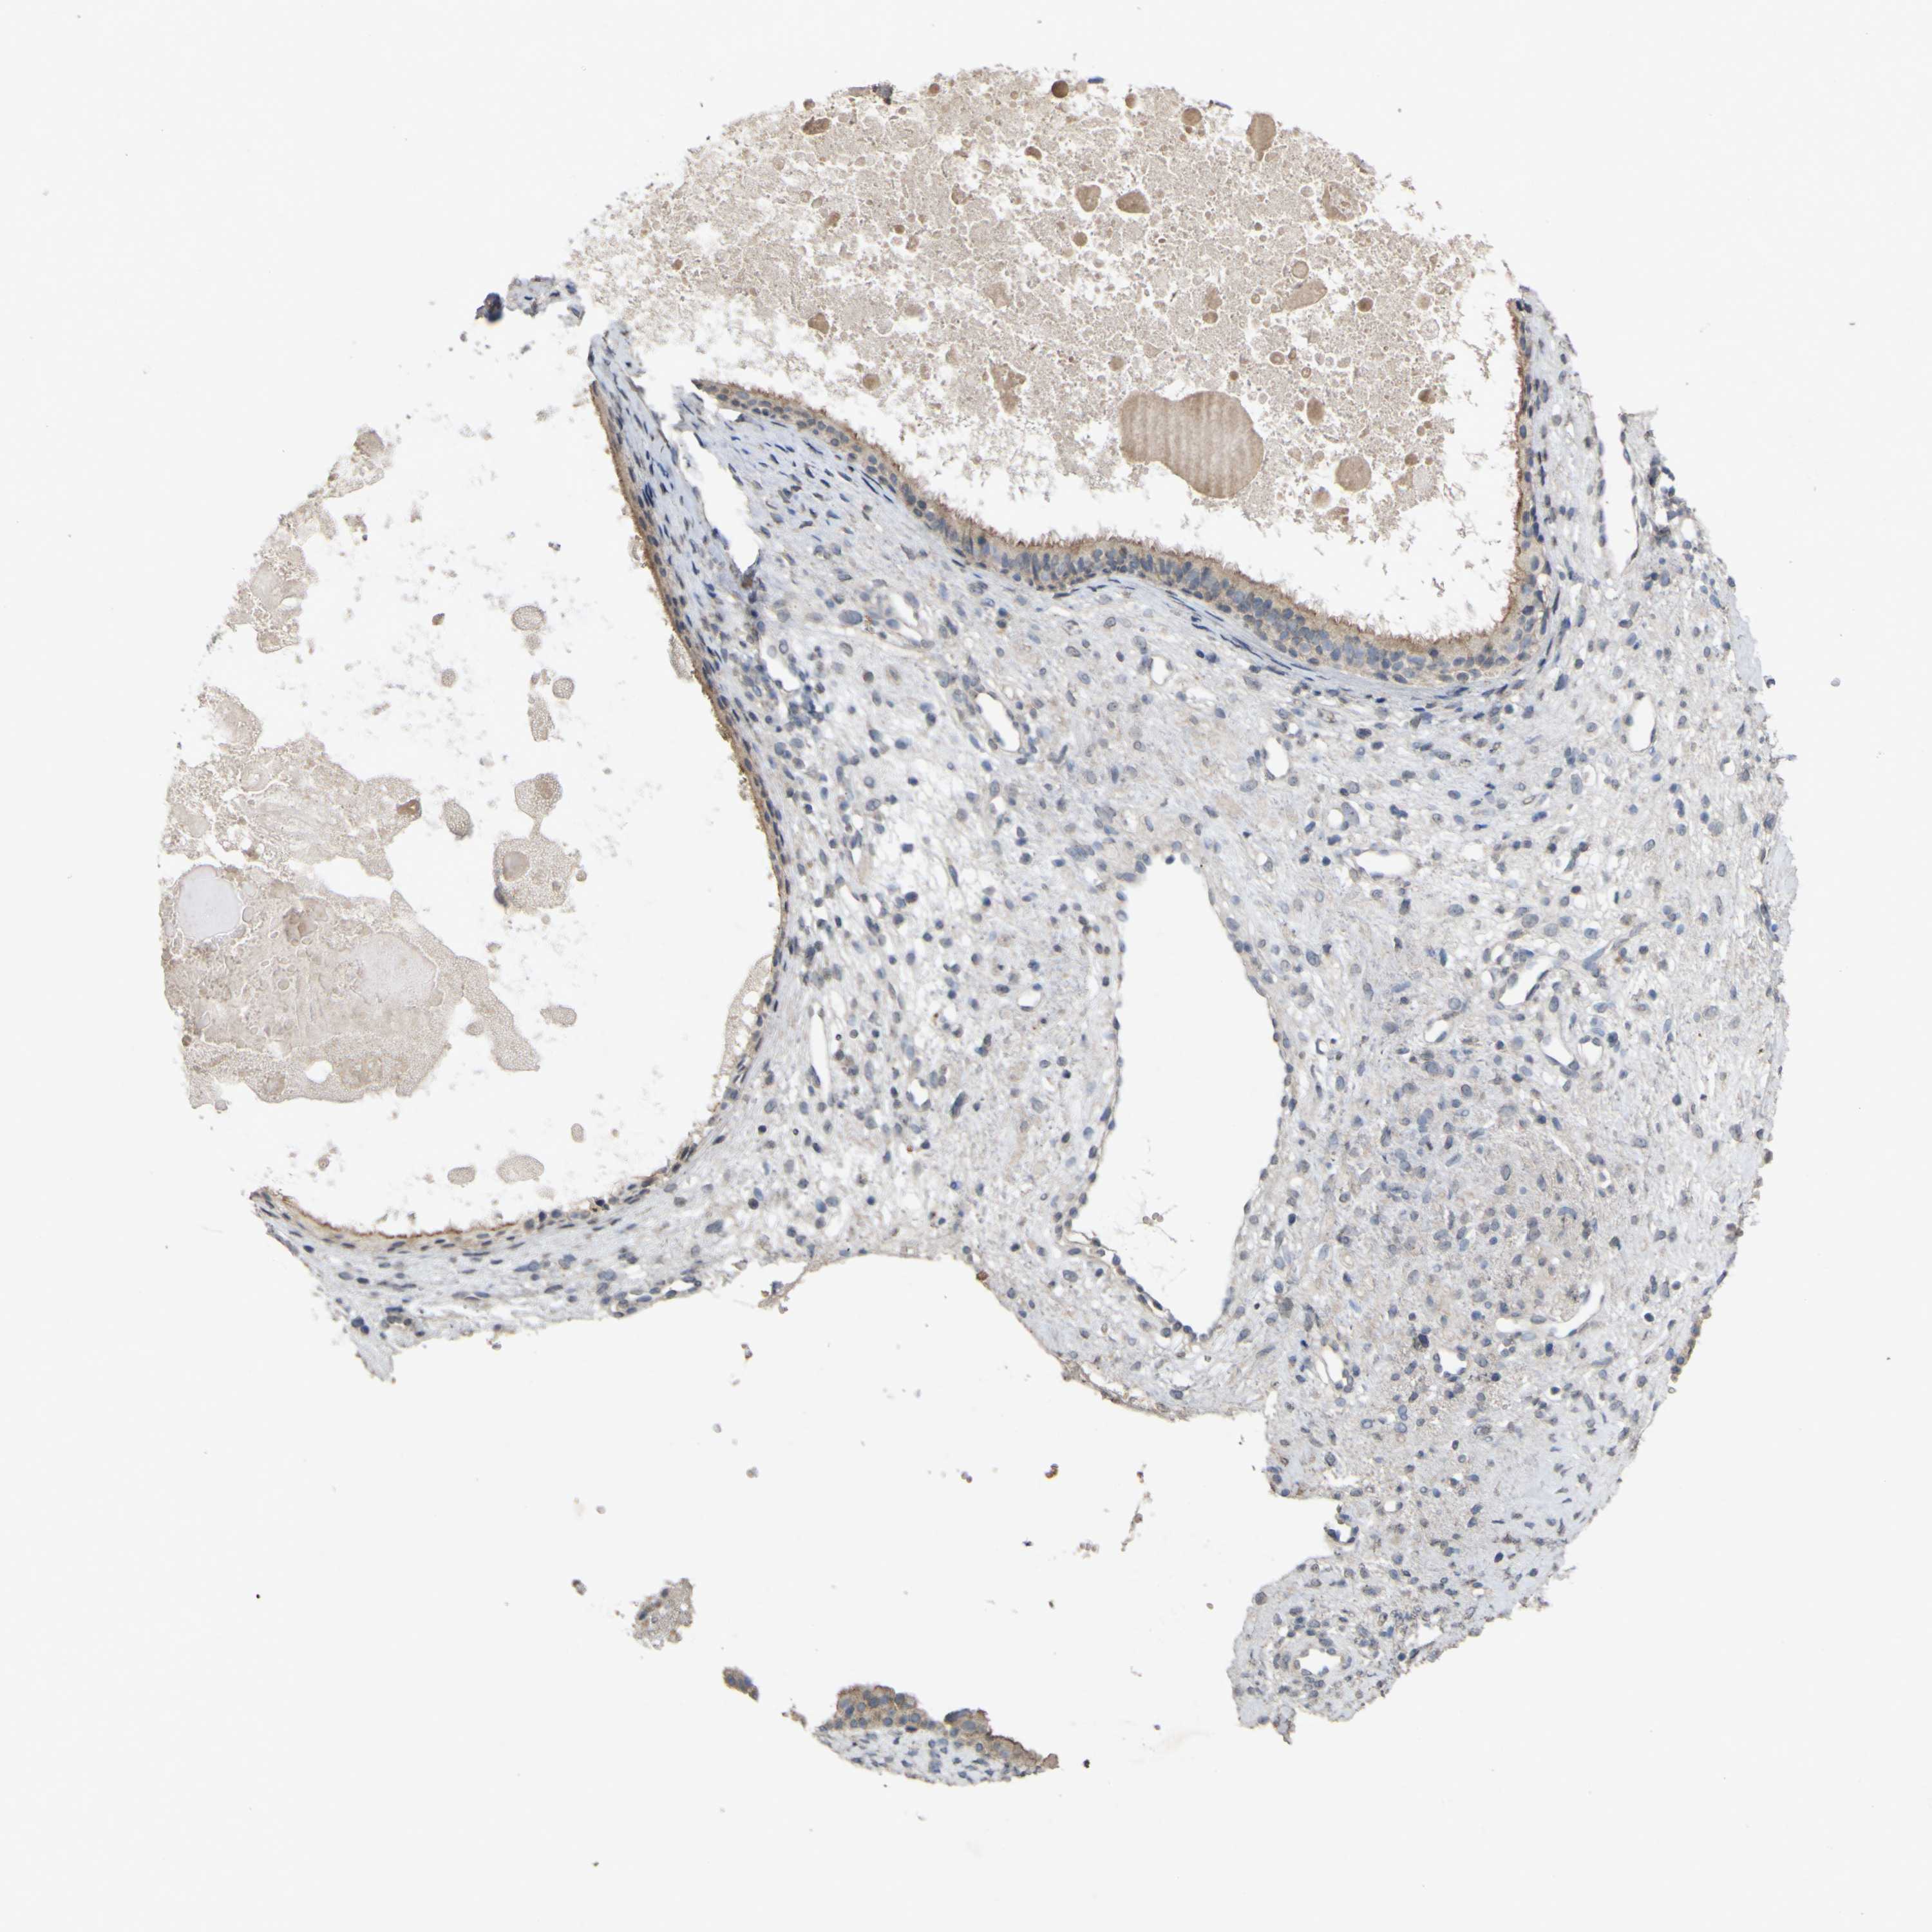

PRKCG